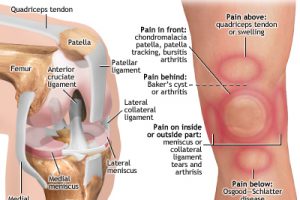

最近もひざの痛みでお悩みの方が多くいらしていますが、パーソナルトレーニングを受けた皆さまから多くいただくお声として「ひざが痛いのは、もも前の筋肉不足以外の原因が沢山あることに気がついた!」ということです。

さらにお伝えすると、同じひざの痛みだとしても、原因は先ほどお伝えしたように「一人一人必要な運動方法が違う」という事です。